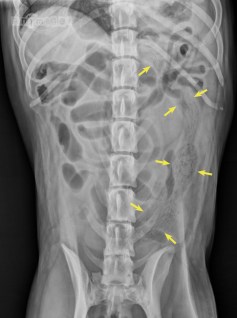

L’image radiographique était bien caractéristique d’un corps étranger textile, soit une structure oblongue formée de lignes irrégulières d’opacité tissulaire entrecoupées de lignes de gaz. Le corps étranger se trouvait aussi dans le côlon sans causer de patron franc d’obstruction. Il est donc sorti assez rapidement sans causer de dommage autre qu’une bonne entérite.